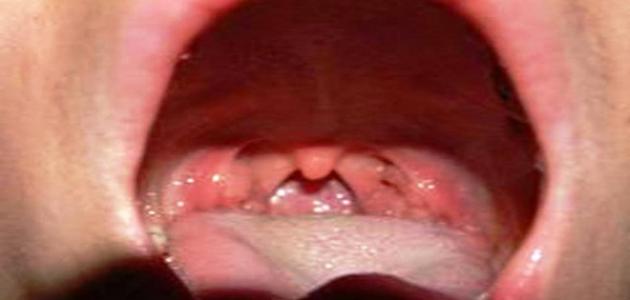

يعتبر لسان المزمار بأنّه صمّام الأمان في جسم الإنسان؛ حيث إنّه قطعةٌ غضروفيّة تشبه أوراق النعناع، وتعمل على الفصل بين الجهاز الهضمي وما بين الجهاز التنفّسي، وتكون متّصلةً بجذر اللسان، ويغطّيها غشاء مخاطي وظيفته منع الطّعام للدخول إلى القصبات الهوائيّة عند تناول الأكل؛ حيث إنّه عندما يختلط الهواء بالطّعام نشرق، وقد يصيبنا ذلك بالاختناق. تركيبة لسان المزمار غضروفيّة ومرنة وقاسية، ولكن أنسجة لسان المزمار مرنة وذلك ناتج عن تكونّه من حزم صغيرة، وغشاء مخاطي يغطّيه ممّا يساعد على أداء وظيفته. تعدّ وظيفة لسان المزمار من أخطر الوظائف في جسم الإنسان؛ حيث إنّه لو دخلت نصف كأس ماء عن طريق الخطأ إلى الرغامي الموجود بالقصبات الهوائيّة لتصل إلى مجرى الرئتين، فإنّ ذلك يؤدّي إلى وفاة الإنسان فوراً ، وذلك لأنّ الخلايا النبيلة في الدماغ تموت موتاً نهائياً في حال توقّف عنها الأكسجين لأكثر من خمس دقائق، أو نزل طعام إلى هذا المجرى بالخطأ، أو نتيجة توقّف لسان المزمار عن أداء وظيفته، وسدّ المجرى لسبّب ذلك اختناق الإنسان وموته.[١]

قد يصاب لسان المزمار بالتهاب اسمه التهاب لسان المزمار، وهو من الحالات الطبيّة الطارئة؛ فقد يؤدّي إلى الموت إذا لم يتم العلاج فوراً، وكما ذكرنا سابقاً عن وظيفته في منع الأكل من الدخول الى القصبات الهوائيّة، فإذا حدث الالتهاب به يتورّم ويؤدّي الى عرقلة دخول الطعام إلى الجهاز الهضمي، وقد يؤدّي إلى انسداد الجهاز التنفّسي، ويحدث التهاب لسان المزمار بعدوى في الجهاز التنفّسي أو التعرّض إلى مواد كيميائيّة أو صدمات خارجيّة عليه، ويبدأ التهاب لسان المزمار على شكل تورّم بين جذر اللسان ولسان المزمار، وقديماً كان الأطفال الصغار هم الأكثر تعرّضاً لالتهاب لسان المزمار، وسبب ذلك قصر قطر لسان المزمار لديهم بالمقارنة مع الانتفاخ في القصبات الهوائيّة، ولكن في سنة 1985م تمّ إعطاء تطعيم يُسمّى بتطعيم ضد المستديمة النزليّة؛ حيث إنّه بعد ذلك انخفض حدوث الالتهاب بصورة كبيرة، وكان يصيب الأطفال ما بين (2-4) سنوات، أمّا الأطفال دون هذا السن فلم تحدث لديهم إصابات بهذا الالتهاب.[٢]